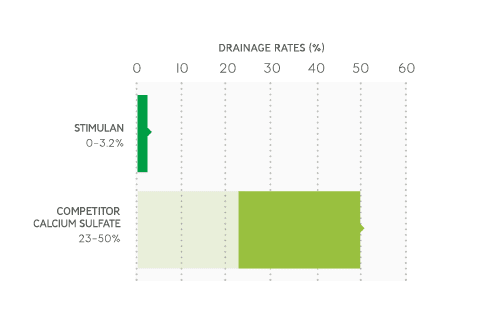

Low levels of drainage2–3, 6–7, 10–12